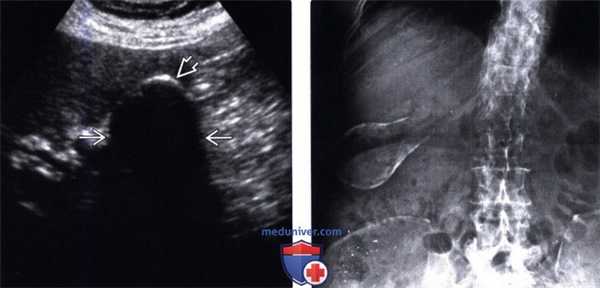

(Левый) Пример полного кальциноза: у пациентки 67 лет, жалующейся на периодические боли в области желчного пузыря, при сканировании в черно-белом режиме в ямке желчного пузыря определяется тонкая гиперэхогенная полулунная линия, отбрасывающая плотную акустическую тень.

(Правый) У этой же пациентки в той же области в правом верхнем квадранте ожидаемо определяется диффузная криволинейная линия кальциноза, повторяющая контуры желчного пузыря.